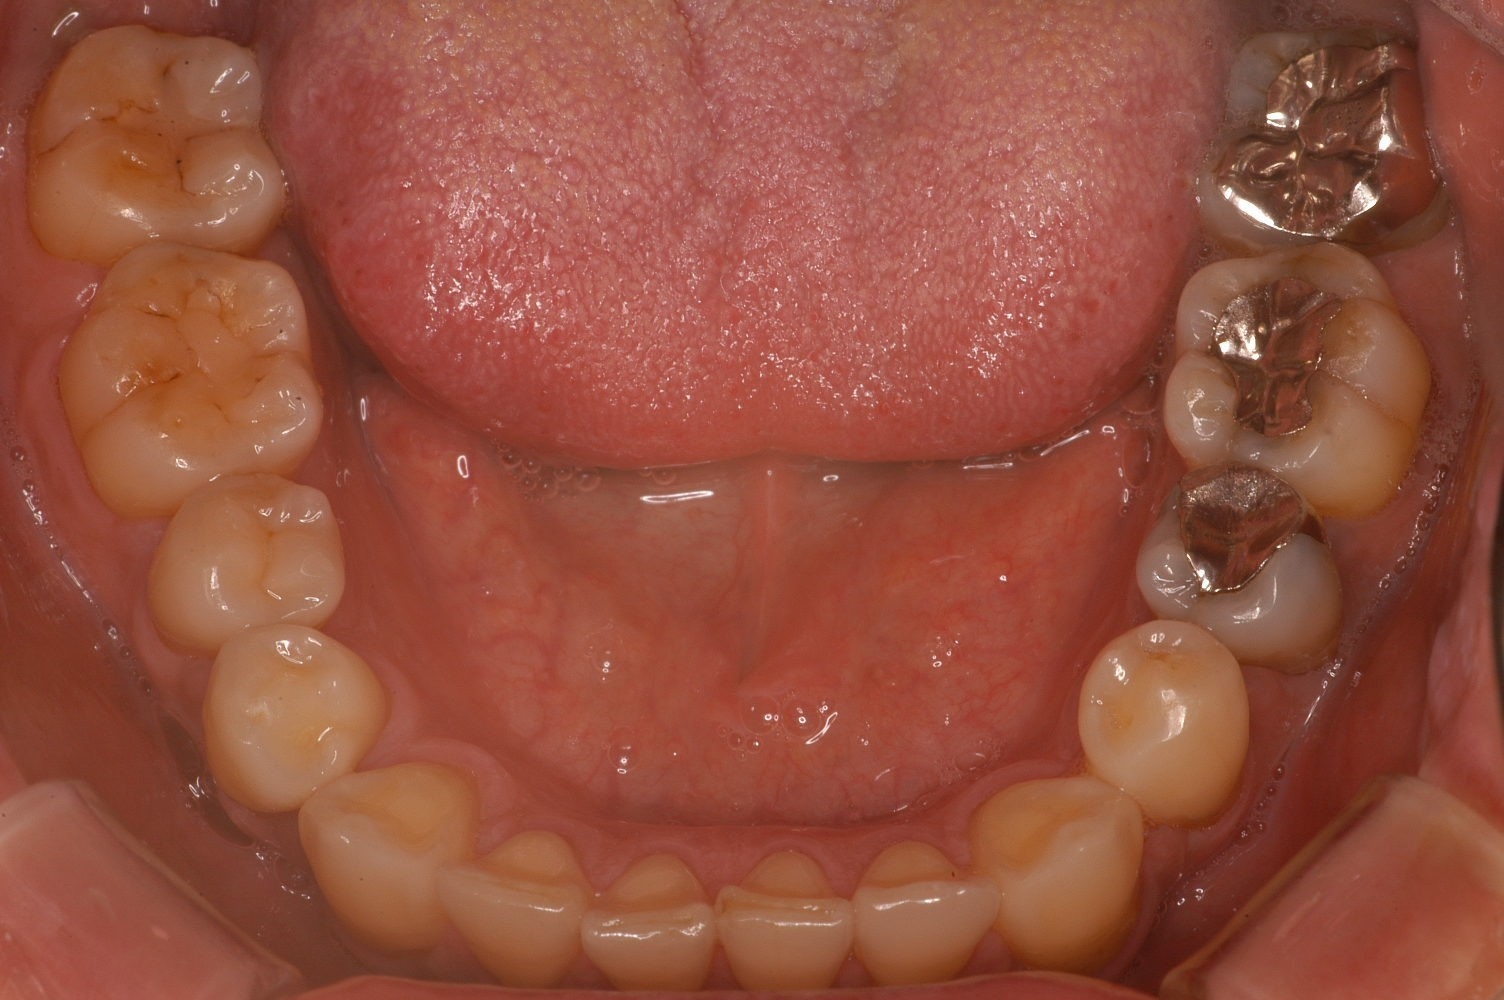

「理想的な歯並び」と「現代人に多い歯並び」の画像、これは何を意味しているのか?

歯並びの中にあるもの。それは、「舌」だったのです。

歯並びが小さいと「舌が窮屈」になり、アゴの位置がずれてしまいます。

その結果、体に様々な症状を引き起こしていたことが分かりました。